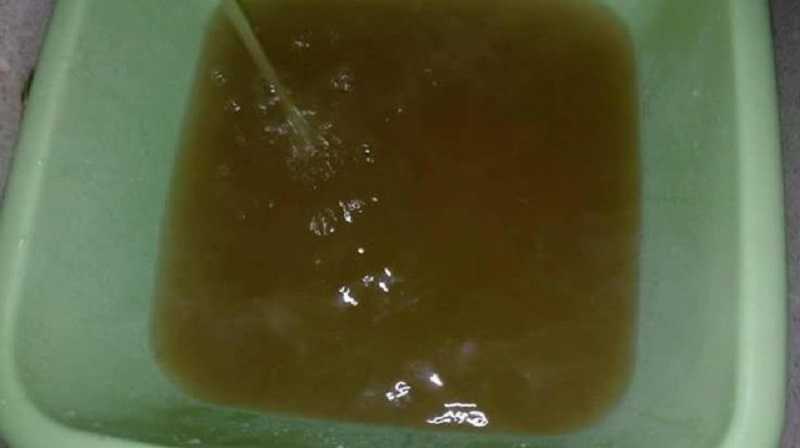

Медицинские аспекты мекония в околоплодных водах